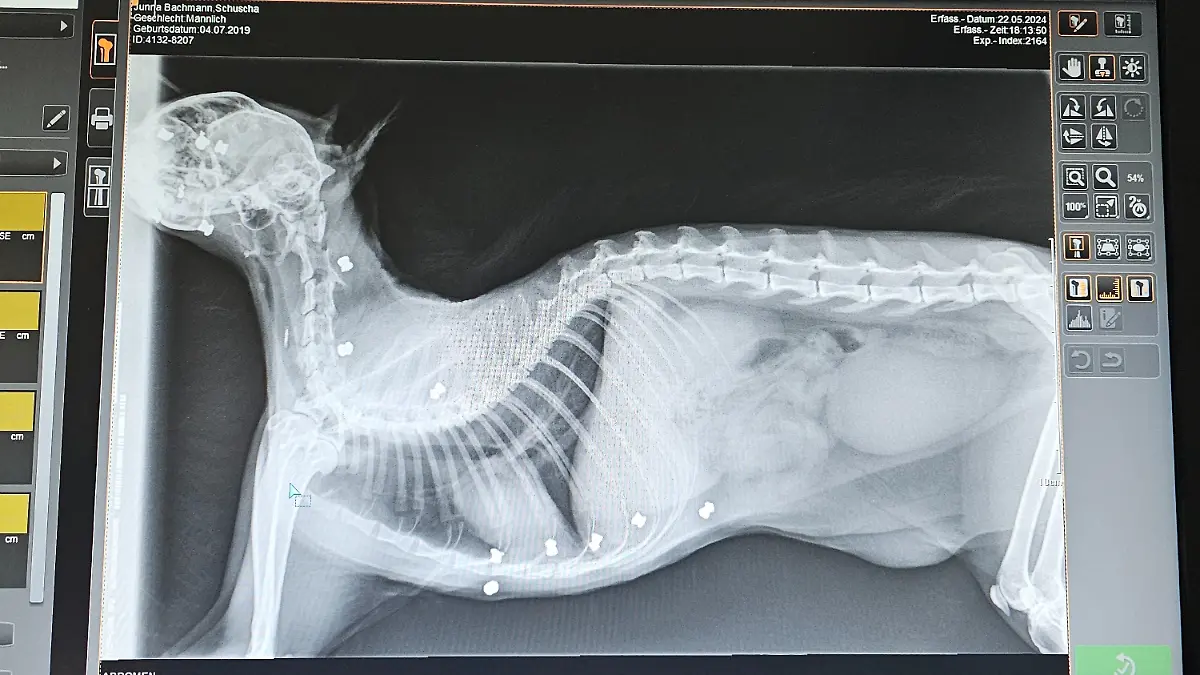

Ihr Instinkt trügt nicht: Nach mehrfachen Tierarztbesuchen bringt ein Röntgenbild Klarheit. Schuscha wurde von 25 Luftgewehrkugeln getroffen. Sein linkes Auge muss entfernt werden. Tierärztin Caroline Schröter spricht von Glück, „dass keine lebenswichtigen Strukturen wie größere Gefäße, vielleicht auch das Herz getroffen wurden.“ Jörg Bachmann vermutet, dass der Schütze vom Kater gestört worden sein könnte. Er glaubt, dass der Täter „ihn dann lebendig gefangen gehalten hat und dann gefoltert, gequält hat, dann draufgeschossen und dann ausgesetzt mit der Hoffnung, dass er nicht überlebt.“

Dank einer Spendenkampagne, die eine Nachbarin organisiert hat, kann die Familie die dringend notwendige OP bezahlen. Doch noch immer stecken 19 Kugeln in Schuschas Körper, eine davon sogar in seinem Gehirn. Wie es der Familie heute geht und was der Kater in Zukunft noch durchmachen muss, erfahrt ihr im Video!